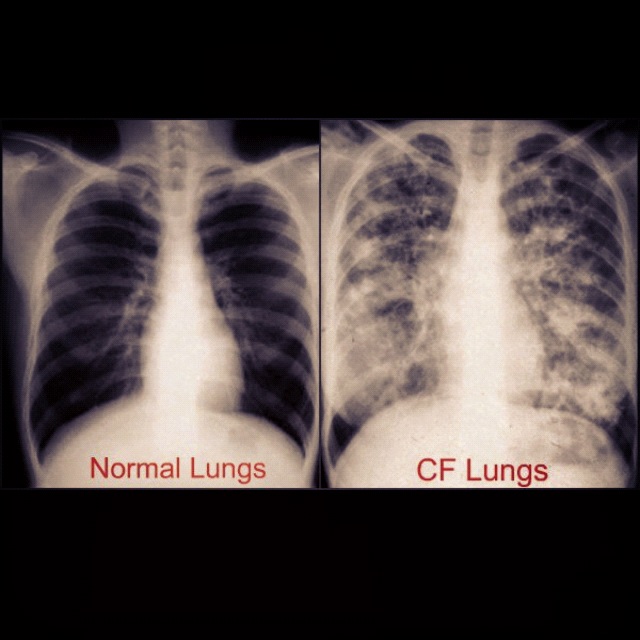

From realheroesbecomeangels.blogspot.com

Real Heroes Angels Keep calm and just breathe What Do Cloudy Lungs Mean The finding can be one small spot all the way to involve the lungs. There are 3 major patterns of pulmonary opacity: ground glass looks hazy or cloudy compared to the normal dark lung. ground glass opacity shows up on lung scans if something, such as swelling or fluid, is partially blocking the air spaces in the lungs.. What Do Cloudy Lungs Mean.